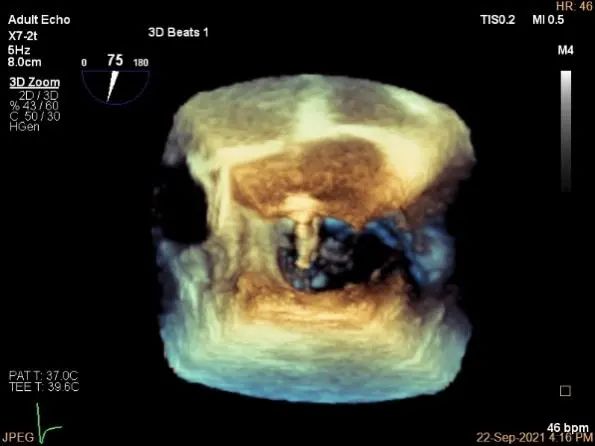

术中超声

P2区脱垂,宽14.8mm,Gap:3.3mm

3D-color,返流重度,3+级

三维评估两个夹子位置

3D-color再次确定未见残余分流